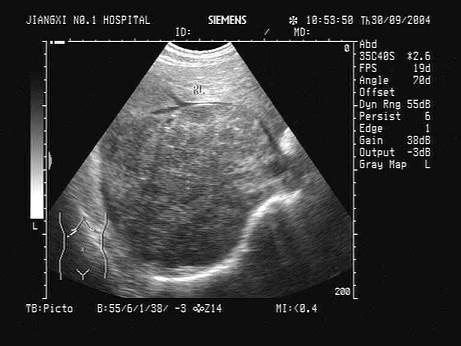

问题 根据肝脏声像图表现,最可能的诊断是?(?)

选项 A.原发性肝癌 B.转移性肝癌 C.肝脓肿 D.肝血管瘤 E.肝囊肿

答案 A